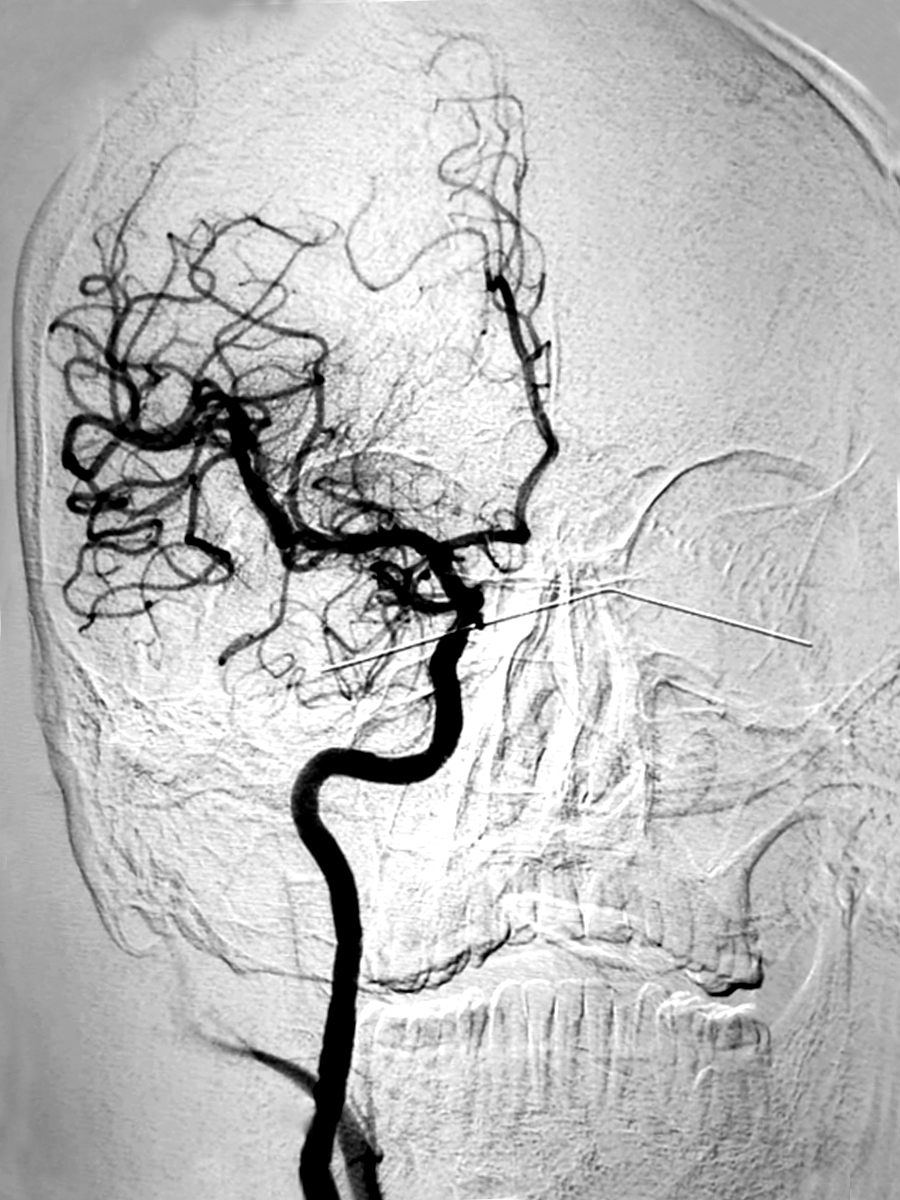

न्युरो इन्टरभेन्सनका अब्बल युवा डाक्टर